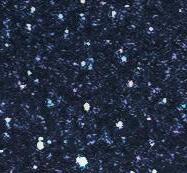

Fig. 2

Verruga Vulgar autoría propia vista microscópica

epiteliales elongados que tienden a converger hacia el centro, se observan coilocitos y células apoptóticas, el estroma

es de tejido conjuntivo laxo bien vascularizado, hacia la base; tejido muscular estriado. (Fig 2). Se diagnóstico como Verruga vulgar cavidad oral.

Nota:Fototomadaporelautor